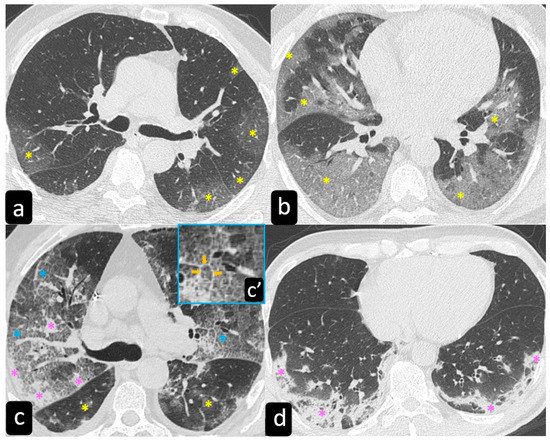

2.2. Typical and Atypical Manifestation of Pulmonary Sarcoidosis at HRCT

3.2. HRCT Findings of Lung Involvement from COVID-19

- Cozzi, D.; Bargagli, E.; Calabrò, A.G.; Torricelli, E.; Giannelli, F.; Cavigli, E.; Miele, V. Atypical HRCT manifestations of pulmonary sarcoidosis. La Radiol. Med. 2018, 123, 174–184. [Google Scholar] [CrossRef]

- Tana, C.; Donatiello, I.; Coppola, M.G.; Ricci, F.; Maccarone, M.T.; Ciarambino, T.; Cipollone, F.; Giamberardino, M.A. CT Findings in Pulmonary and Abdominal Sarcoidosis. Implications for Diagnosis and Classification. J. Clin. Med. 2020, 9, 3028. [Google Scholar] [CrossRef] [PubMed]

- Larici, A.R.; Cicchetti, G.; Marano, R.; Merlino, B.; Elia, L.; Calandriello, L.; Del Ciello, A.; Farchione, A.; Savino, G.; Infante, A.; et al. Multimodality imaging of COVID-19 pneumonia: From diagnosis to follow-up. A comprehensive review. Eur. J. Radiol. 2020, 131, 109217. [Google Scholar] [CrossRef]